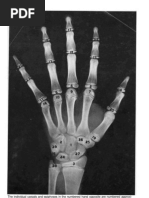

Wrist disarticulation ►amputation through the ►should begin as soon as possible after surgery

TERMINAL DEVICE: object in the closed position, but rather uses the semi-open

Functional activities of the hands: position to facilitate the interaction with the environment.

1. Non-prehensile activities ►This is why a VC device is said to be more physiological

2. Prehensile activities:

2.1 precision VOLUNTARY CLOSING HOOK/TERMINAL DEVICE

2.2 power grips ►provides a degree of graded prehension

1. Non-prehensile activities 1. pulling the control cable closes the hook partially or fully

►include touching, feeling, pressing down with the fingers, 2. releasing the control cable tension causes the hook to

tapping, vibrating the cord of a musical instrument, and lifting lock in the attained position

2. Prehensile activities: open

►three jaw chuck: involves grips with the thumb, index and ►functional

middle finger ►APRL hook was developed by the Army Prosthetics

►a lateral or key grip: involves contact of the pulp of the Research Laboratory after World War II